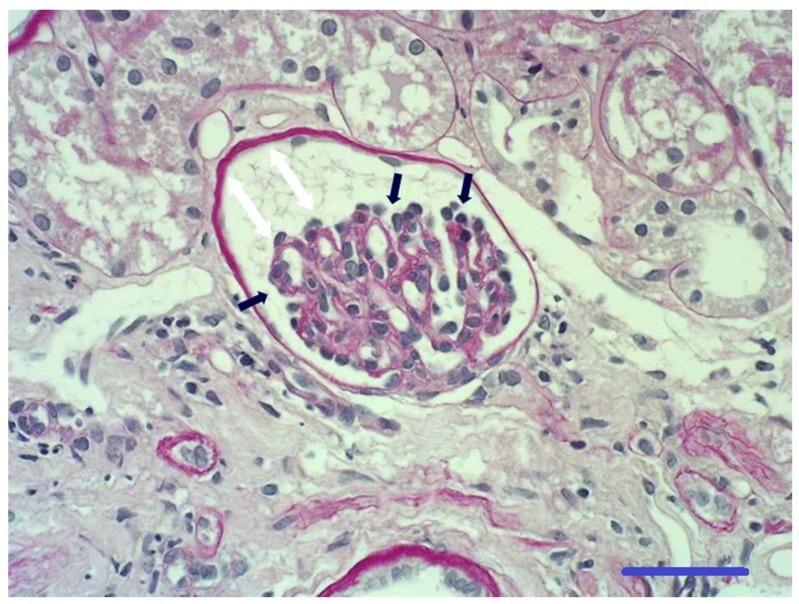

Renal maldevelopment (RM) has been proposed to replace the old and sometimes misused term "renal dysplasia" in dogs. Although renal dysplasia has been described in Boxers, hereditary transmission has only been hypothesized. This study reports clinical and renal histological findings in Boxer dogs with RM, proposing a possible mode of inheritance. Medical records of 9 female Boxer dogs, older than 5 months and with a clinical diagnosis of chronic kidney disease prior to one year of age, were retrospectively reviewed. Polyuria and polydipsia (PU/PD), decreased appetite, weight loss, lethargy and weakness were described in all affected dogs. Common laboratory findings were proteinuria, diluted urine, non-regenerative anemia, azotemia, hyperphosphatemia, hypoalbuminemia and hypercholesterolemia. Histopathology of the kidneys revealed the presence of immature glomeruli in all dogs, which is consistent with RM. In 7 related dogs, the pedigree analysis showed that a simple autosomal recessive trait may be a possible mode of inheritance. Renal maldevelopment should be suspected in young Boxer dogs with a history of PU/PD, decreased appetite, weight loss, lethargy, weakness and proteinuria. Due to its possible inheritance, an early diagnosis of RM may allow clinicians to promptly identify other potentially affected dogs among the relatives of the diagnosed case.

有人提议用肾发育不全(RM)取代犬类中旧的且有时被误用的术语“肾发育异常”。尽管拳师犬中已描述了肾发育异常,但遗传传递仅为推测。本研究报告了患有RM的拳师犬的临床和肾脏组织学发现,提出了一种可能的遗传模式。回顾性分析了9只5个月以上、1岁前临床诊断为慢性肾病的雌性拳师犬的病历。所有患病犬均出现多尿和多饮(PU/PD)、食欲减退、体重减轻、嗜睡和虚弱。常见的实验室检查结果为蛋白尿、尿液稀释、非再生性贫血、氮质血症、高磷血症、低白蛋白血症和高胆固醇血症。肾脏组织病理学检查显示所有犬均存在未成熟肾小球,这与RM一致。在7只相关犬中,系谱分析表明简单的常染色体隐性性状可能是一种可能的遗传模式。对于有PU/PD病史、食欲减退、体重减轻、嗜睡、虚弱和蛋白尿的年轻拳师犬,应怀疑肾发育不全。由于其可能的遗传性,RM的早期诊断可能使临床医生能够迅速在确诊病例的亲属中识别出其他可能受影响的犬。